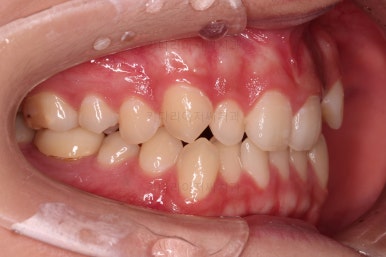

마찬가지로 초진 시 입안의 모습인데요.

위아래 앞니가 삐뚤고, 송곳니는 덧니처럼 불룩 튀어나가 있네요.

위아래 앞니는 안으로 굽어 들어와 있는 옥니(뻐드렁니 반대) 양상이었고요.

그리고 마무리 때 디테일에 문제가 생길 수 있는 부분인데, 윗니 대문니(가장 중간 치아)와 송곳니 사이의 치아를 작은 앞니라고 하는데요.

이 작은 앞니가 가져야 될 크기보다 더 작은 양상이었습니다.

이런 치아를 왜소치라교 표현합니다.